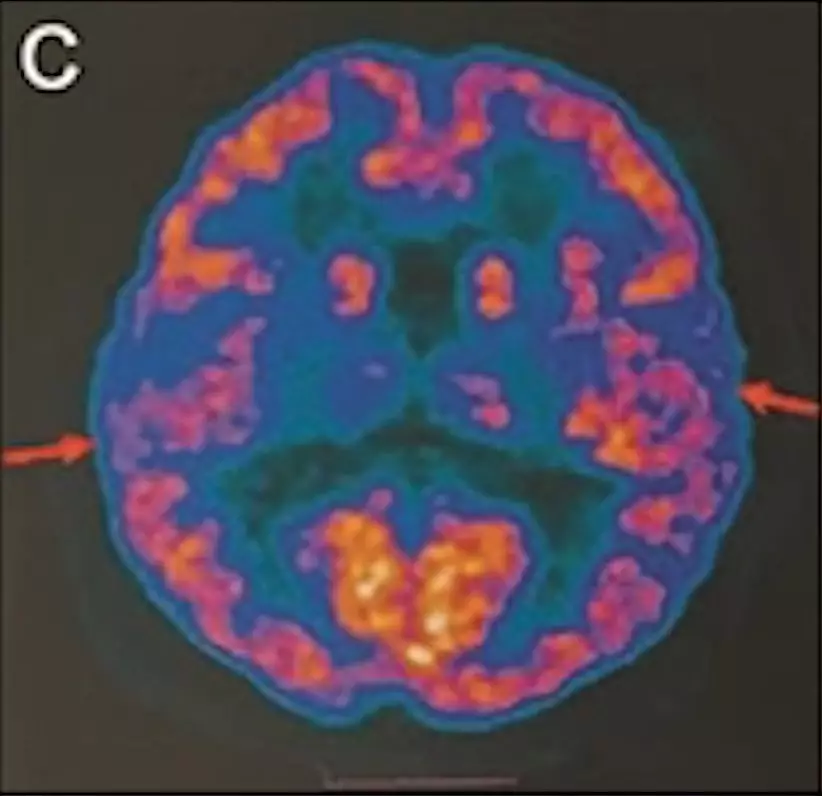

最年輕的19歲阿茲海默症男子腦部掃描結果:

該名19歲男子到醫院接受多項檢查,包括腦脊液指標檢測及正電子掃描。結果顯示,他出現輕度腦萎縮等症狀,最終被臨床診斷為「阿茲海默症」。